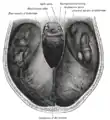

Артерии основания головного мозга.

Диаграмма артериальной циркуляции основания головного мозга.

Намёт мозжечка. Вид сверху.